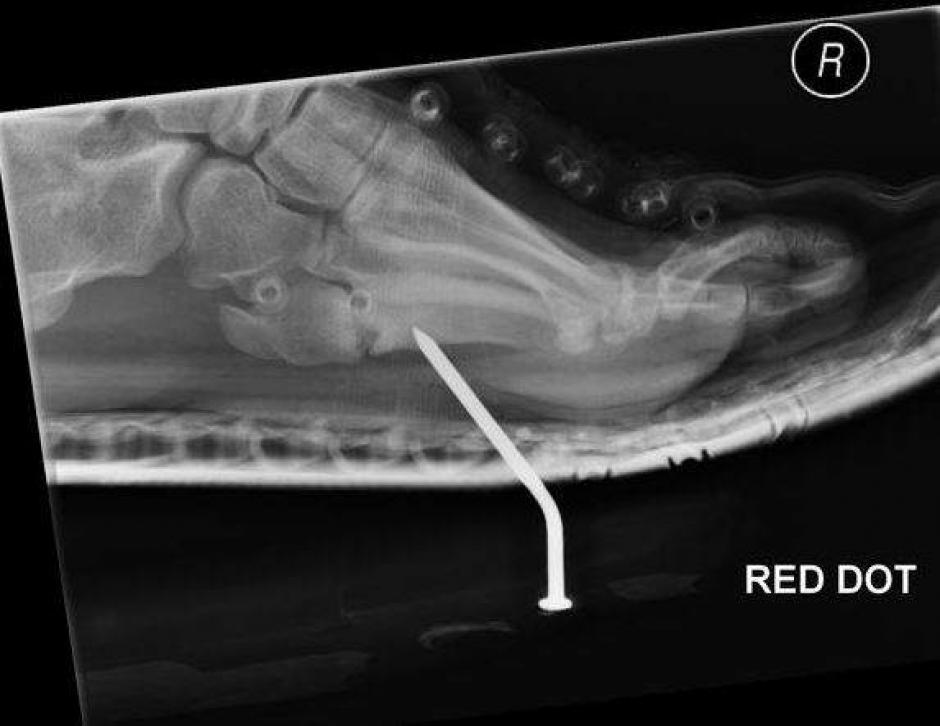

También hay varios ejemplos de heridas traumáticas, desde palos hasta balas pasando por espinas de pescado.

Aquí el bote con alfileres. ¿A quién se le ocurre?